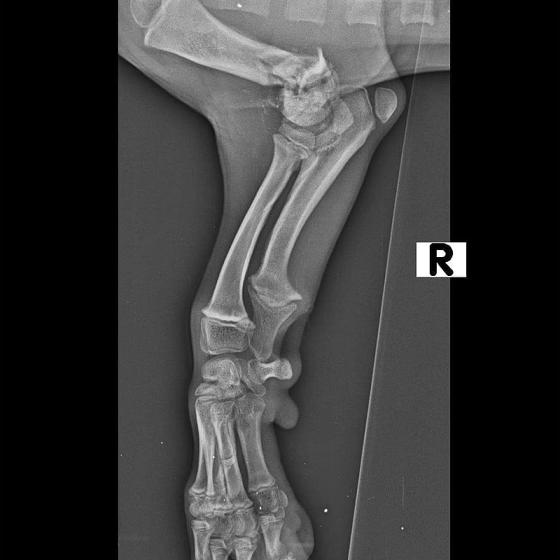

Pluto dnes absolvoval druhú operáciu. Vyberala sa platnička a veľká skrutka, ktorá sa nahradila menším pinom. Koncom mesiaca ho čaká ďalšia a dúfame, že už posledná operácia. Také malinké šteniatko a už toľko bolesti musí prežívať :( Má sa dobre, rastie do krásy a už sa pomaly može naplno šantiť so svojim kamošom v dočasnej opatere. :) Veľmi pekne prosíme, pomôžte nám s úhradou faktúr. Faktúry nájdete priebežne v galérii a na konci článku aj zoznam darcov s prijatou aj chýbajúcou sumou. Po poslednej operácii čakajú Pluta ešte mesiace rehabilitácie, aby sa nožička úplne rozhýbala a mohol ju používať naplno :)

Odoberal sa od drogovo závislých asociálov, ktorý boli vysťahovaný z domu. Ihly, striekačky, ľudské výkaly, rôzne neidentifikovateľné zvratky, špinavé oblečenie, použité kondómy - to všetko nahádzané na jednu kopu v obývačke, kde Pluto so svojou maminkou Miou žili. :( Nevieme ako sa to stalo, kto mu ublížil, ale Pluto má prestrelenú prednú nohu! Viete si predstaviť toho psychicky narušeného človeka, ktorý strieľa na malé bezbranné šteniatko? V dôsledku strelnej rany má doslova rozdrvenú lakťovú kosť. Mali sme veľké obavy, že o nožičku príde, ale MVDr. Vatolík s teamom veterinárnej kliniky Sibra centrum opäť urobil zázrak a malému nožičku napravil a prognóza je viac než dobrá. Čaká ho ešte dlhá cesta k zotaveniu, ale je to odvážny a statočný bojovník. Nechceme si ani len predstaviť čím všetkým si tie zvieratká muesli prejsť, a kto vie koľko ich pôvodne bolo.. Nikto nevie ako a kde skončili Plutovi súrodenci...